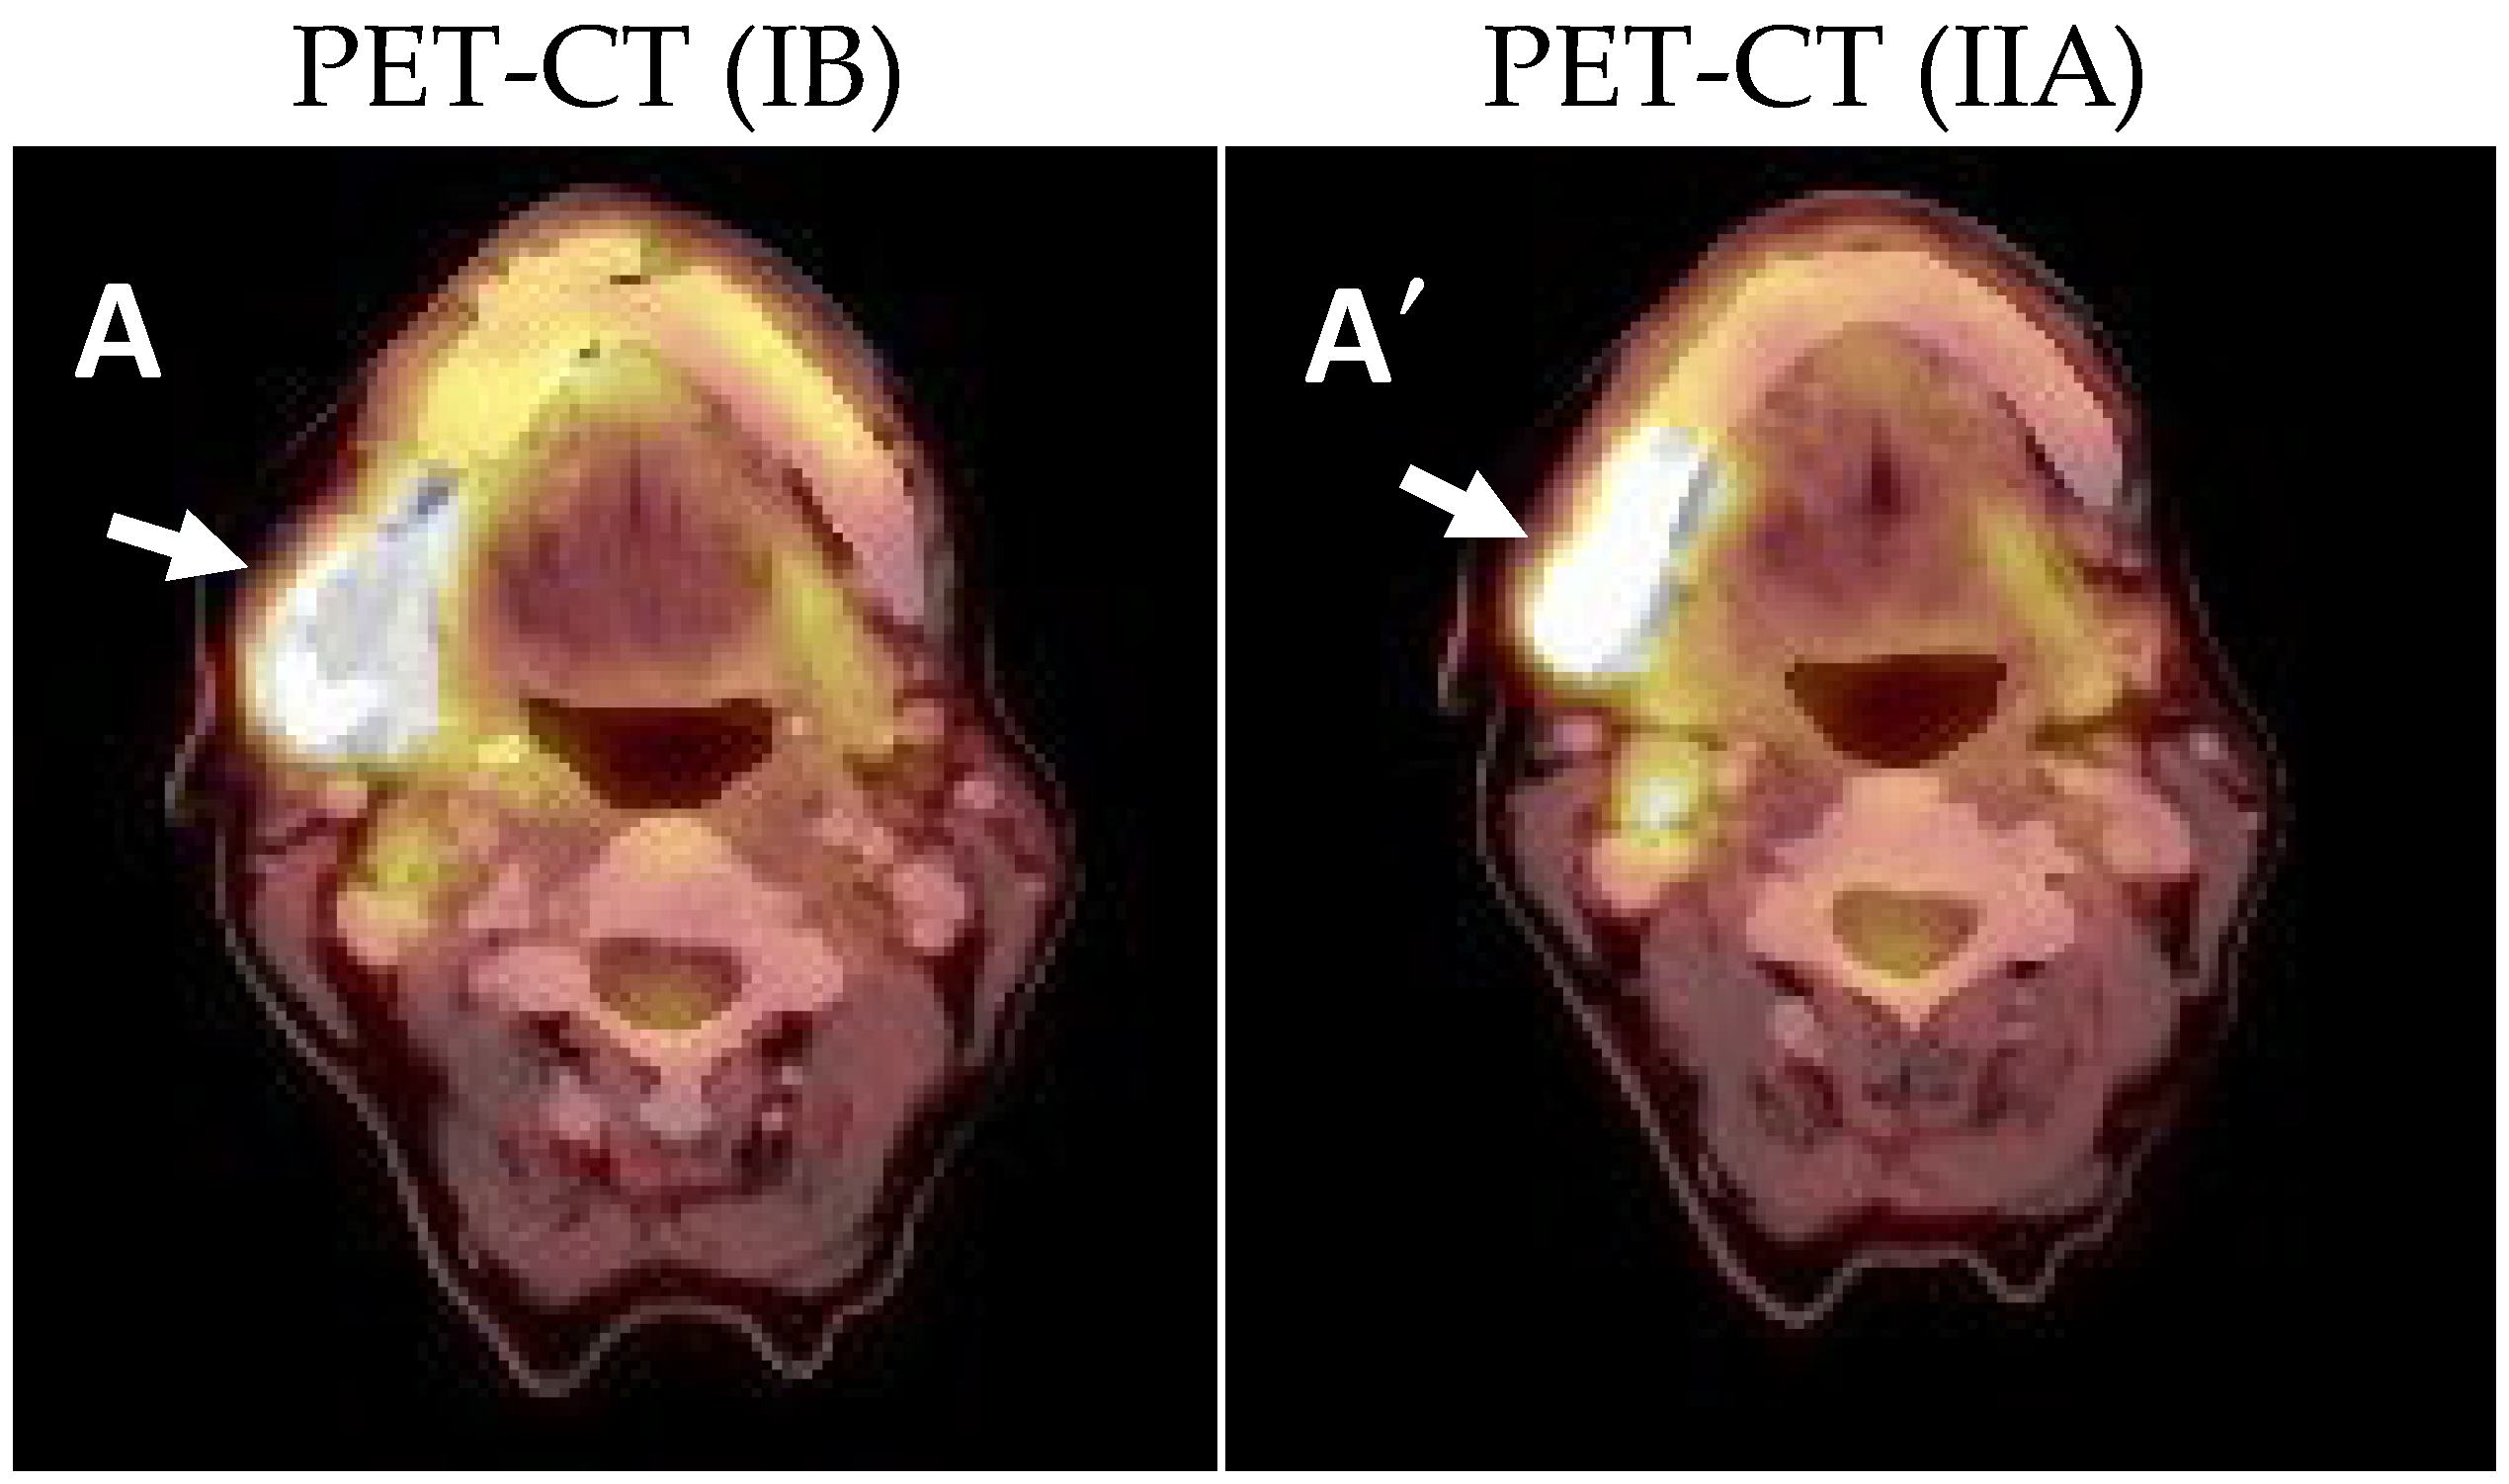

2.1. Clinical and Histological Manifestations of the Tumors

4.3. Positron Emission Tomography-Computed Tomography